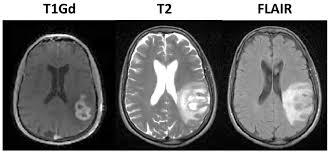

How can we get a clear idea of the extent of cerebral edema in a pt through imaging?

T1 will give us good idea of location of lesion

T2 really highlights extent of edema